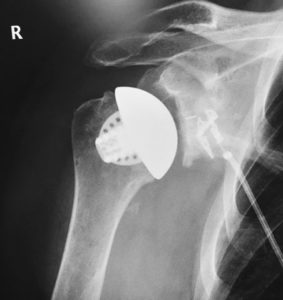

The Equinoxe Stemless Shoulder is a bone conserving prosthesis designed for anatomic total shoulder arthroplasty.

Equinoxe Stemless Shoulder